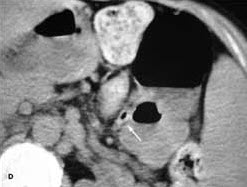

A CT scan of the abdomen and pelvis with oral and intravenous contrast revealed a 5-cm abscess (a) on the left side of the abdomen (A). Adjacent images showed tubular extensions of the abscess, one of which likely represented the appendix. Of note, jejunal bowel loops can be identified by their frond-like appearance on the right side of the abdomen (A, arrow). Normally, the duodenum crosses the midline between the aorta (Ao) and the superior mesenteric artery (S)--a more cephalad image reveals that the most medial extent of the duodenum does not cross the midline (B, arrow). A CT scan performed 6 months earlier during an evaluation for renal stones showed no abscess. Scout view from the prior CT scan demonstrated partially air-filled colon only on the left side of the abdomen (C).

Appendicitis usually presents with right lower quadrant symptoms that occasionally start or remain in the midline. Inflamed elongated appendices can mimic pelvic pathology because of their caudal extent. In patients with malrotation, the small and large bowels do not undergo their normal development and fixation. The small bowel remains on the right side of the abdomen, while the large bowel and appendix are on the left (D, arrow, prior CT scan of same patient). Patients with malrotation only have a nonrotated bowel. In patients with situs inversus, all the abdominal organs are on the opposite side of normal. Patients who have situs inversus totalis have all their abdominal and thorax structures on the "wrong" side.